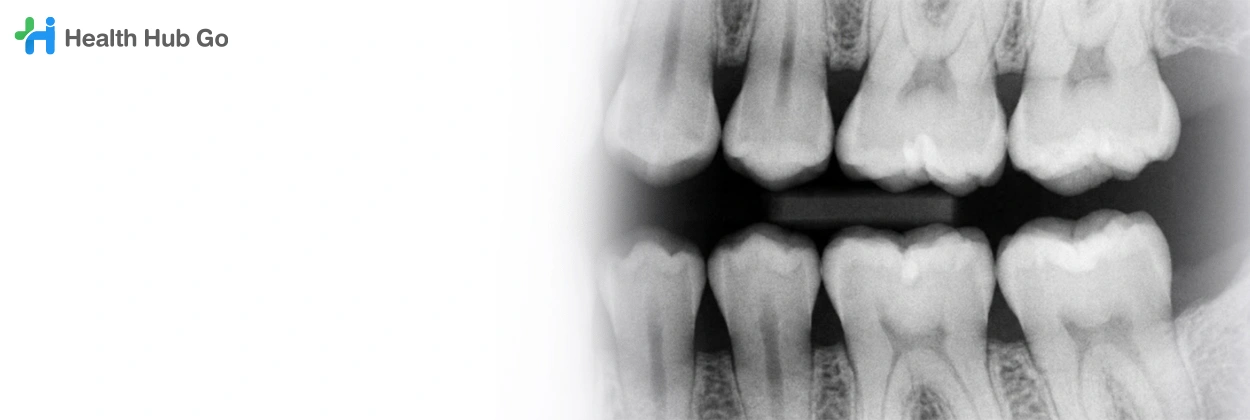

เอกซเรย์ฟัน

เอกซเรย์การสบฟัน

Occlusal X-ray